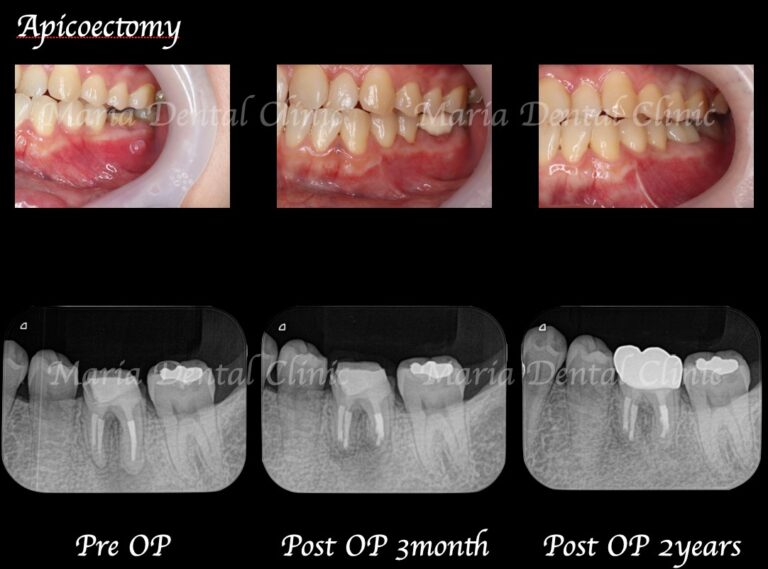

【歯根端切除術】

根管治療を行っても良くならない場合の外科的歯内療法

精密根管治療を施しても治癒に至らない場合、もしくは、被せ物を外すことが困難な場合(装着して間もない被せ物など)は歯根端切除術にて根尖性歯周炎を治癒に導くことが可能です。現代の歯根端切除術の成功率は90%以上で、破折していない歯であれば保存することが可能です。しかし、外科処置なのでリスクも当然あります。当院では精密根管治療初回カウンセリングにてご自身の歯の状態や診断から精密根管治療(歯内療法)後のリスクをお話した上で、治療介入を行うか患者様に決めていただいております。

副作用・リスク

• 下歯槽神経を損傷した場合、顔面に知覚麻痺が生じる場合があります

• 術中に予期せぬ歯根破折が確認された場合、処置は中止させていただくことがあります